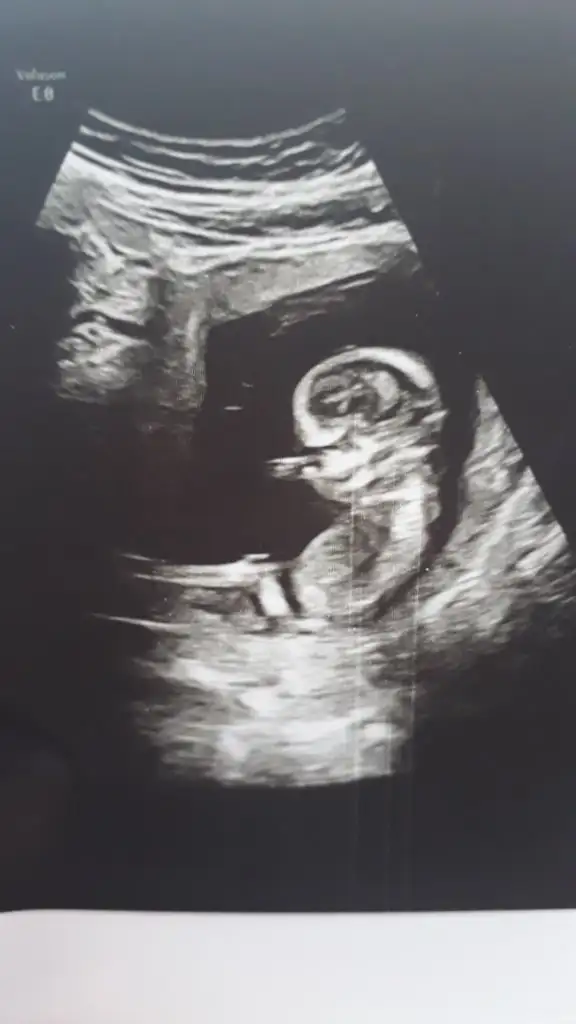

Erkek görünüyorKızlar selamlar bebişime bakar mısınız rica etsem. Çok merak ediyorummdoktor kesin birşey söylemedi. Bir çıkıntı var dedi. 1 ay daha bekliycem. Buradan anlaşılır mı? 3. Fotoyu hiç anlamadım. Çok teşekkürler sevgiler

Buna göre erkek görünüyor ama en iyi 11 12 13 haftalar olmalıMerhabaIkra meyra , benim ultrason görüntülerime de bakabilir misiniz lütfen?

Teşekkür ederimBuna göre erkek görünüyor ama en iyi 11 12 13 haftalar olmalı